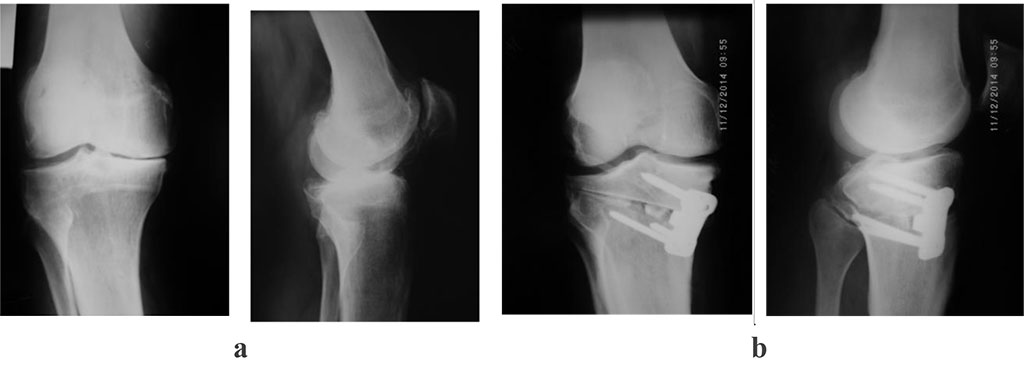

Patient P. is 55 years old. She referred to the clinic with complaints of pain and deformation in the right knee joint. At the time of reference, several clinical trials were carried out, according to the results of which a diagnosis was made: Left-sided gonarthrosis of the III stage varus deformities of the left knee joint (Fig. 1). The patient underwent a supratuberous valgus osteotomy of the right tibia, with bone autoplasty and МОС ХМ plate (Fig. 2)

Figure 1: photoprints of radiographs of patient P., 55 years old, with a diagnosis of III stage left-sided gonarthrosis. varus deformities of the left knee joint. a – before surgery; b - after surgery: supratuberous valgus osteotomy of the right tibia, with bone autoplasty and МОС ХМ plate